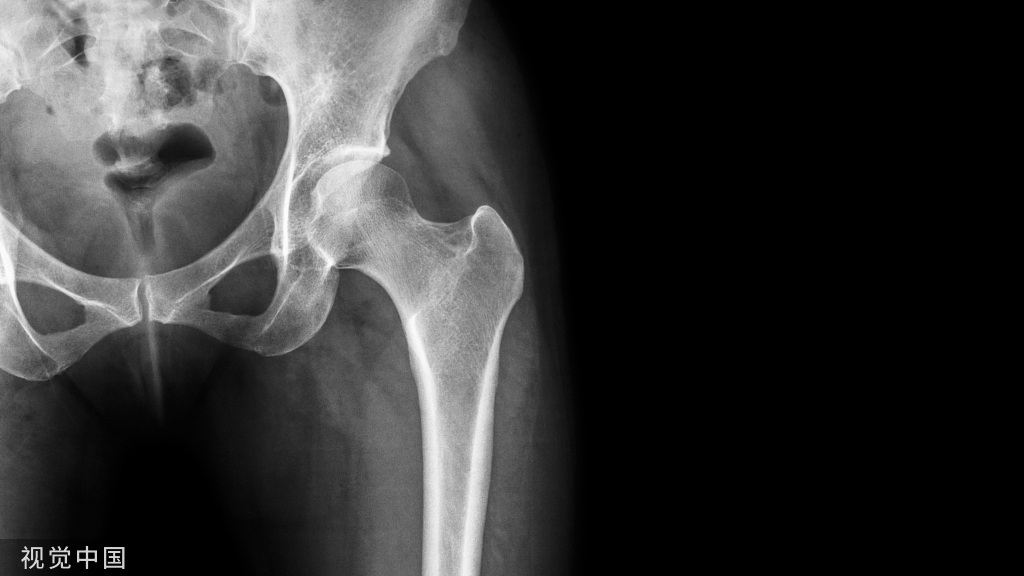

以2号或5号爱惜邦线缝合附着于冠状突骨块的前关节囊,尺骨嵴做一小切口。自后向前打2个骨孔,分别位于冠状突骨折基底的两侧,使用硬膜外套管针和细钢丝辅助将缝线两端分别经骨孔拉至尺骨背侧,再以2枚(或数枚,视术中情况而定)直径为1.5mm的克氏针自后向前打入。针尖位于骨折基底处,复位冠状突,以这2枚克氏针进行固定;针尾折弯剪短后埋于皮下,再在尺骨后方拉紧缝线并打结固定(如图2,冠状突骨折和前关节囊的处理)。对于损伤严重的患者,前方软组织自尺骨近端前方剥脱,造成肱尺关节有脱位趋势。此时前方关节囊的张力比冠状突的骨性稳定更重要,通过这一方法可维持较好的肱尺关节稳定性。由于冠状突骨折块通常较小,使用螺钉固定容易造成骨折块碎裂,不能获得有效固定,因此不建议使用。肘关节三联征损伤时的冠状突骨折绝大多数为尖部骨折,属于Regan和Morrey分型的Ⅰ度或Ⅱ度损伤,O' Driscolll分型的Ⅰa型或Ⅰb型,一般不超过高耸结节,因此MCL的尺骨附力点常保持完整。通常无需采用内侧支撑钢板固定冠状突骨折。